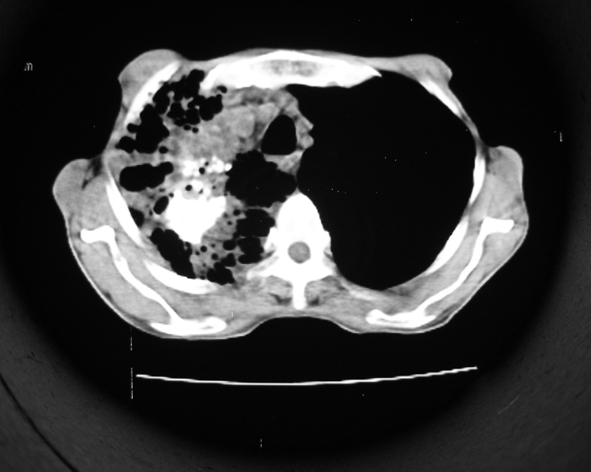

男53岁,咳嗽气短,以往身体健康.

右肺上叶多发多形态空洞及增殖灶,可见团块钙化,胸膜肥厚、粘连,考虑继发型肺结核可能性大

1.右肺上叶干酪性肺炎,2。肺气肿,肺大泡

1.右肺上叶干酪性肺炎,2。肺气肿,肺大泡。支持!

支持右上肺继发性肺结核并干酪性肺炎,右肺大泡,左肺代偿性气肿。